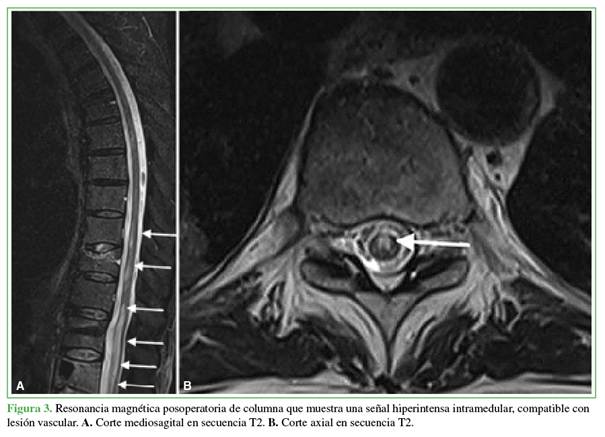

A las 48 h de la cirugía inicial, una resonancia magnética de columna, de urgencia, reveló hiperintensidad intramedular no compresiva compatible con isquemia medular extensa desde T9 hasta L4 (Figura 3). Se la consideró una lesión medular de manejo no quirúrgico; por lo tanto, se reinició el esquema de anticoagulación y se derivó al paciente a un centro de rehabilitación intensiva.

El infarto medular es una complicación neuroquirúrgica infrecuente, pero con una morbilidad extremadamente alta. Se presenta el caso de un hombre de 68 años con múltiples comorbilidades oncológicas (cánceres de pulmón y próstata en actividad) y cardiovasculares que desarrolló una paraplejía aguda rápidamente progresiva, tras una biopsia ósea por punción, fijación percutánea y cifoplastia bipedicular en L1. A pesar de que, con la tomografía computarizada, se descartaron causas mecánicas o fuga de cemento, la resonancia magnética confirmó una isquemia medular desde T9 hasta L4. Este reporte analiza la etiología multifactorial del evento, destacando la interacción entre el estado de hipercoagulabilidad paraneoplásica y la técnica quirúrgica, como puntos clave por tener en cuenta en la planificación prequirúrgica.

Spinal cord infarction is an infrequent neurosurgical complication but is associated with extremely high morbidity. We report the case of a 68-year-old man with multiple cardiovascular and oncological comorbidities (active lung and prostate cancer) who developed rapidly progressive acute paraplegia following percutaneous bone biopsy, percutaneous fixation, and bipedicular kyphoplasty at L1. Although computed tomography ruled out mechanical causes and cement leakage, magnetic resonance imaging confirmed spinal cord ischemia extending from T9 to L4. This report analyzes the multifactorial etiology of the event, highlighting the interaction between paraneoplastic hypercoagulability and the surgical technique as key factors to be considered during preoperative planning.